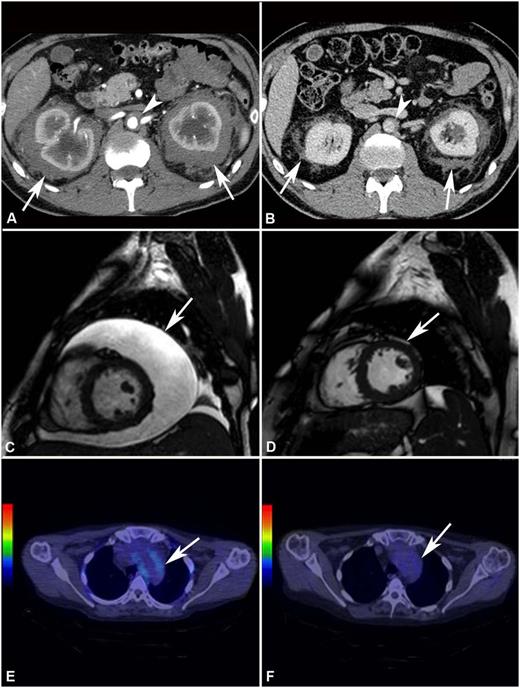

Response to treatment assessed by different imaging modalities. (A) Abdominal CT performed before treatment and (B) after 4 years of SRL and PDN treatment in patient #2. The scans show marked shrinkage of peri-renal (arrows) and peri-aortic fibrosis (arrowhead). (C) Cardiac MRI (T2-weighted, fat-saturation sequence, sagittal view) performed before treatment and (D) after 12 months of treatment with SRL and PDN in patient #10. The scans show neither recurrence of pericardial effusion (arrow) (the patient had also undergone pericardiocentesis) nor signs of pericardial infiltration. (E) 18F-FDG PET-CT performed before and (F) after 12 months of treatment with SRL and PDN in patient #10. The scans (axial view) show disappearance of 18F-FDG uptake at the thoracic aorta level (aortic arch) (arrow).

The remaining 8 patients showed PRs of at least one involved site. Retroperitoneal lesions regressed partially in 4/8 cases and completely in 1/8 (Figure 1 and supplemental Figure 2): at last follow-up, only 2 patients had double-J ureteral stents, and the patient with repeat bowel obstructions (patient #1) no longer developed such complications. Cardiovascular lesions improved in 3/4 cases: the 2 patients with severe pericarditis (one of whom was previously described28 ) underwent pericardiocentesis and remained free of pericardial effusion over the entire follow-up (Figure 1). Bone disease usually remained stable, although an improvement at 99Tc-scintigraphy was observed in 3 cases (Figure 2). CNS lesions progressed in patient #6 and stabilized in patient #3, whereas in patient #7 there was no recurrence of the surgically excised brain mass, and the remaining nodules showed partial regression (supplemental Figure 3). Lung involvement stabilized in all cases. The outcome of the remaining disease manifestations is reported in Table 2. Systemic symptoms improved in most patients; the only patient who experienced persistent systemic manifestations was patient #8. C-reactive protein levels also tended to decrease over time (supplemental Figure 4).